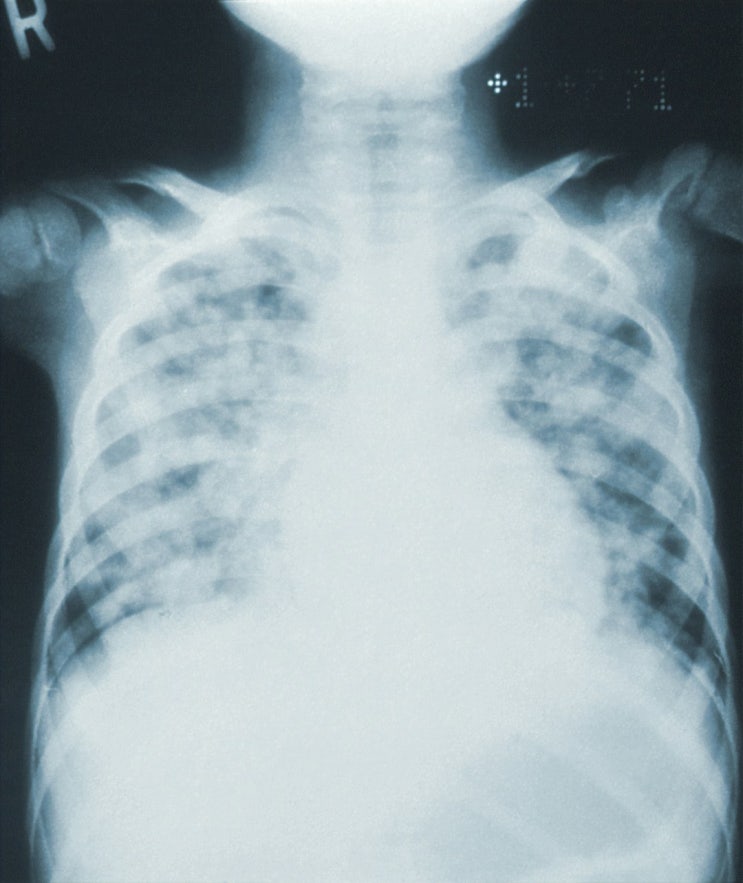

중학생 폐렴 증상 이유 없는 고열 초기 증상

저희 가족은 폐렴을 한 번도 걸려 보지 않은 상황이라 폐렴에 대해 별생각이 없었는데요. 아이가 이틀 전 ...